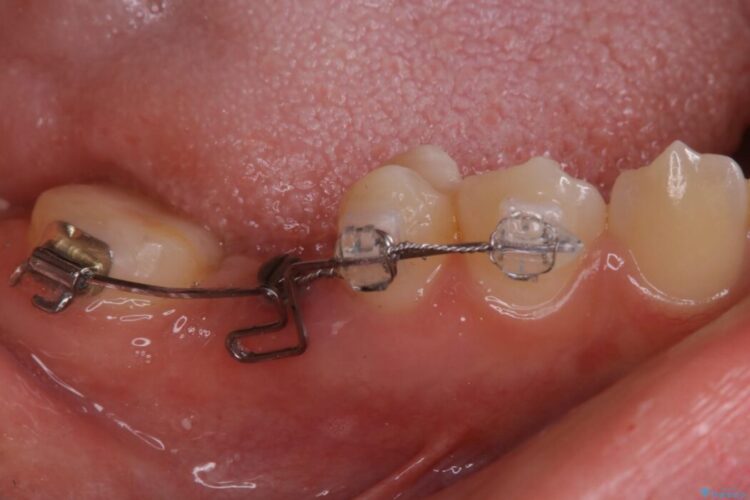

この状態のままブリッジ治療へと進んでしまうと神経が露出する可能性が否定できないため、まずワイヤー装置による部分矯正で歯軸を通常位置へ戻してから補綴治療を行うこととしました。

欠損した部分が補綴され、普通に噛めるようになったと喜んでいただけました。

本症例では、健康な歯を可及的に守るため神経の処置を避けた上で部分矯正を併用して行うことにより、安全に補綴治療(ブリッジ)ができました。